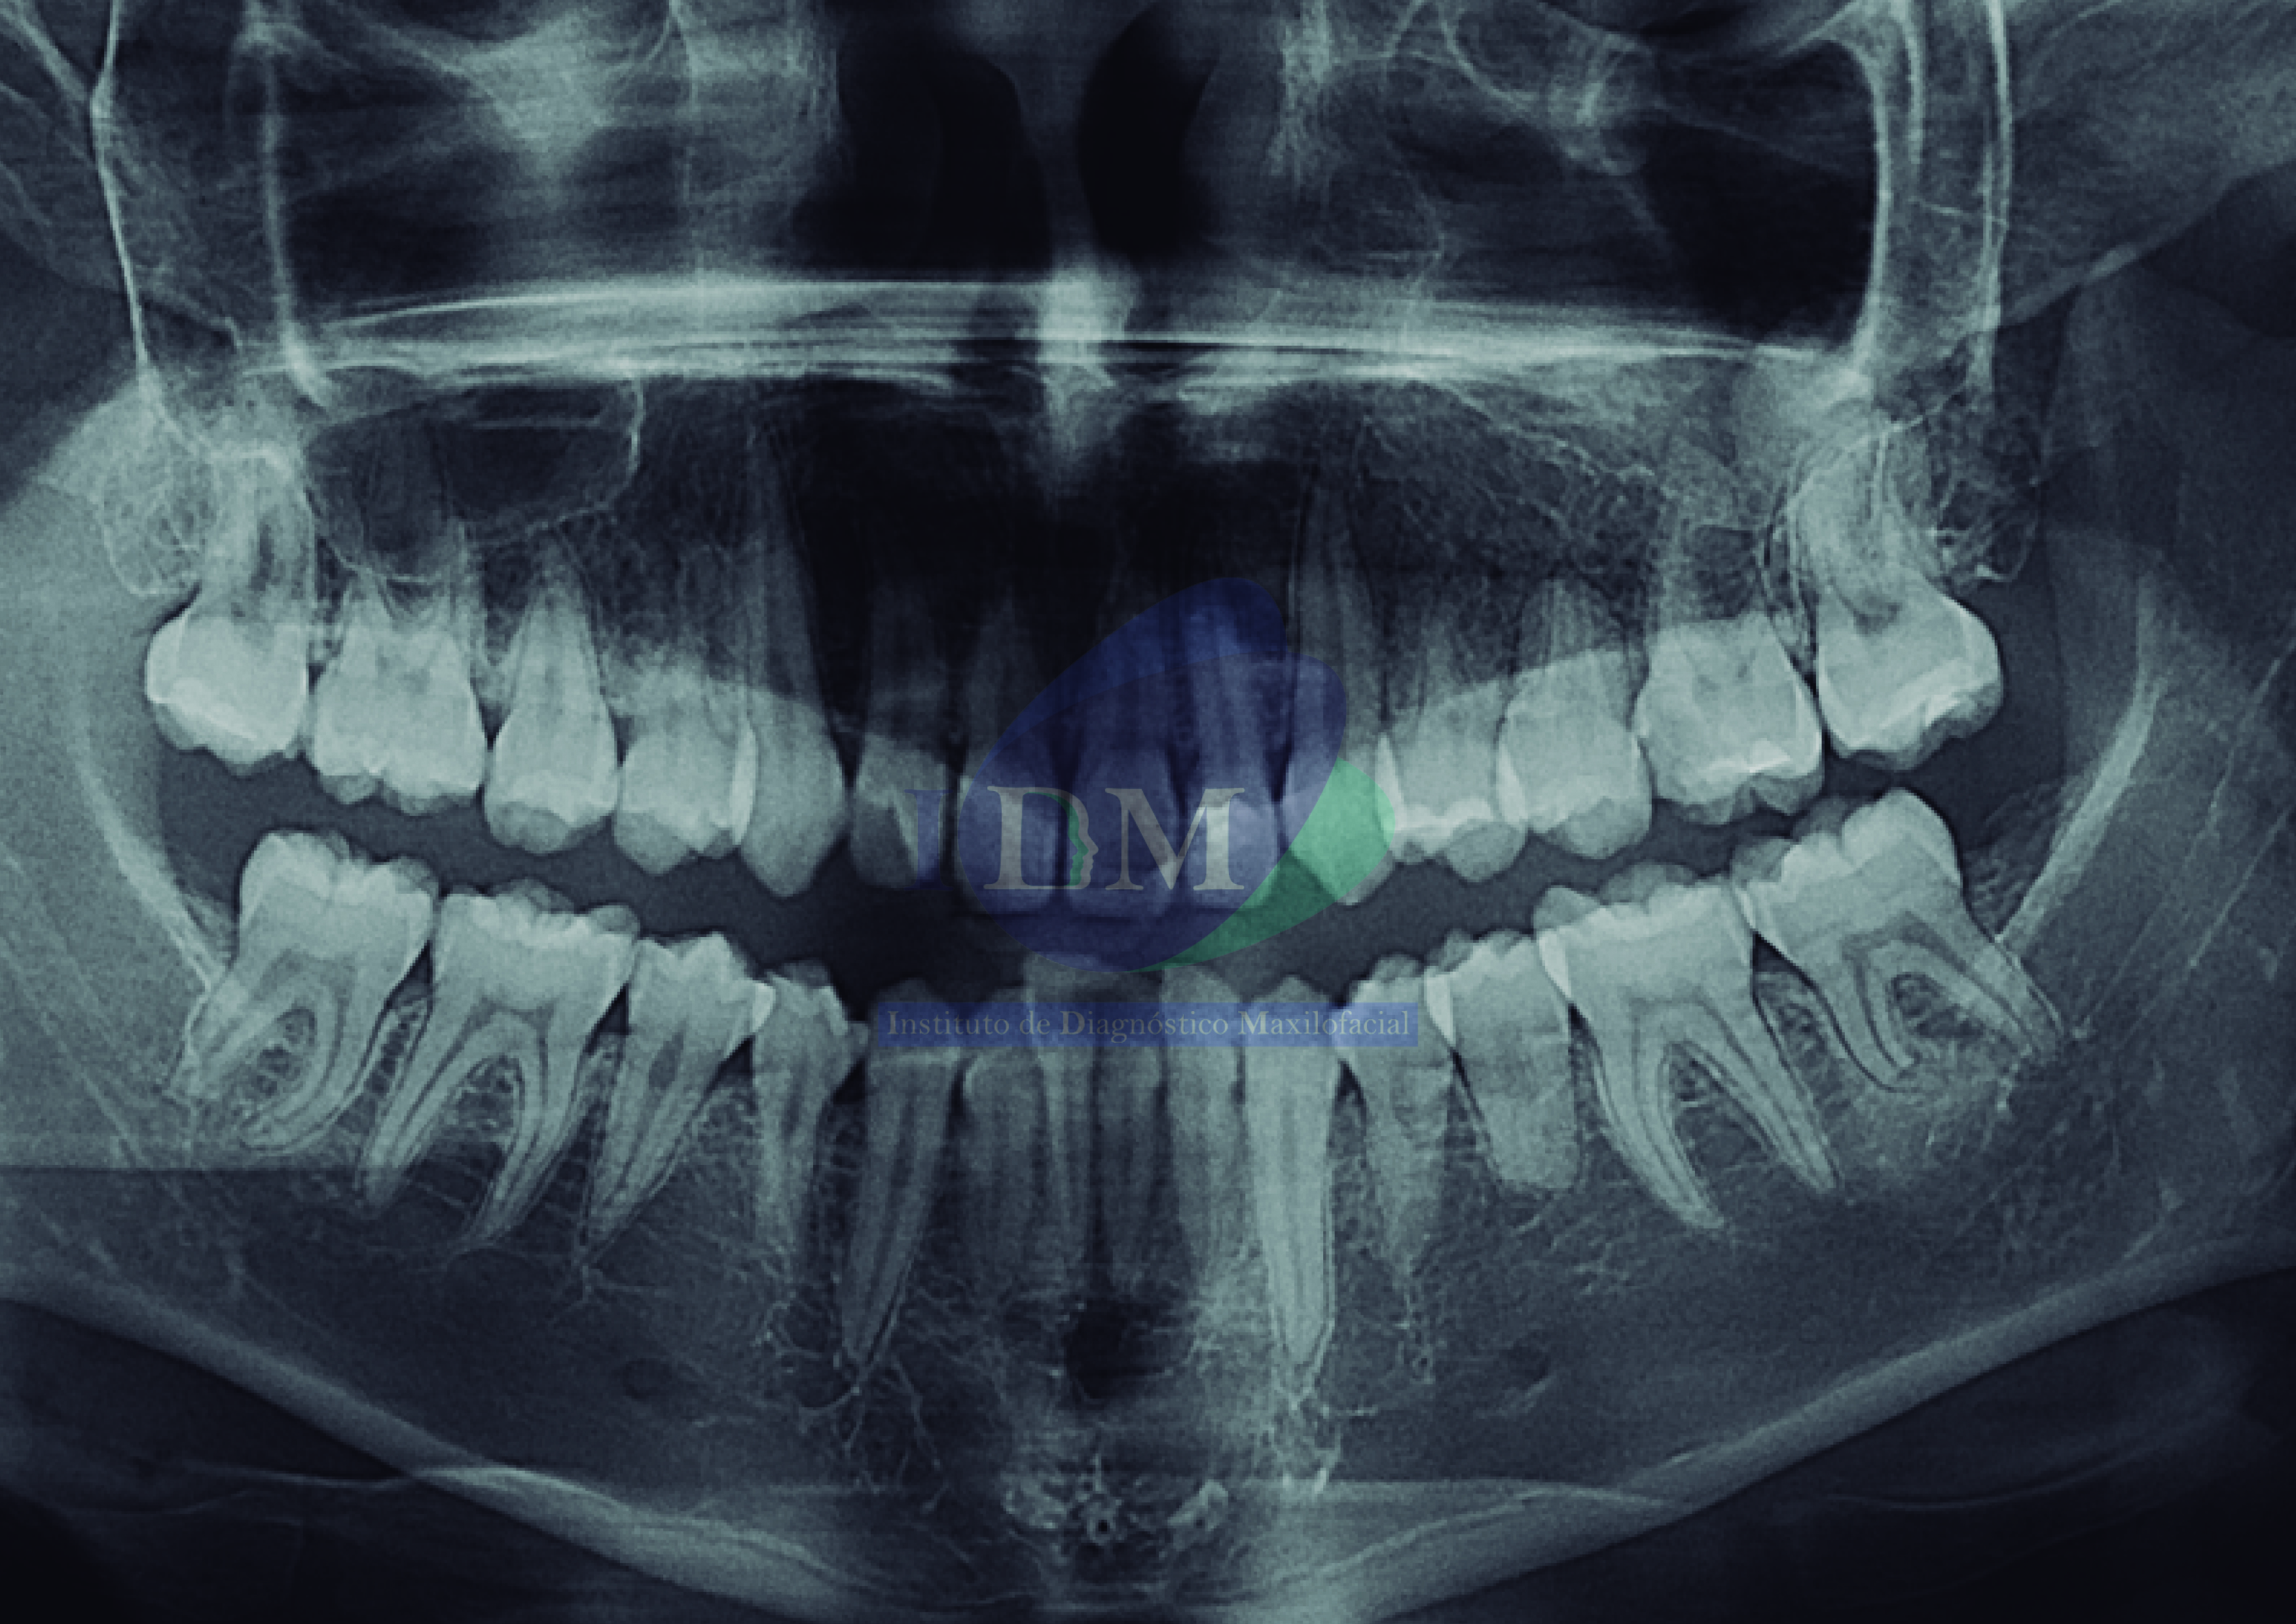

Caso 286 – IDM – MESIODENS RETENIDO IDM

Paciente masculino de 51 años acude al Instituto de Diagnóstico Maxilofacial (sede Miraflores) para evaluación integral. Radiografia Panorámica A la evaluación de la radiografía panorámica se